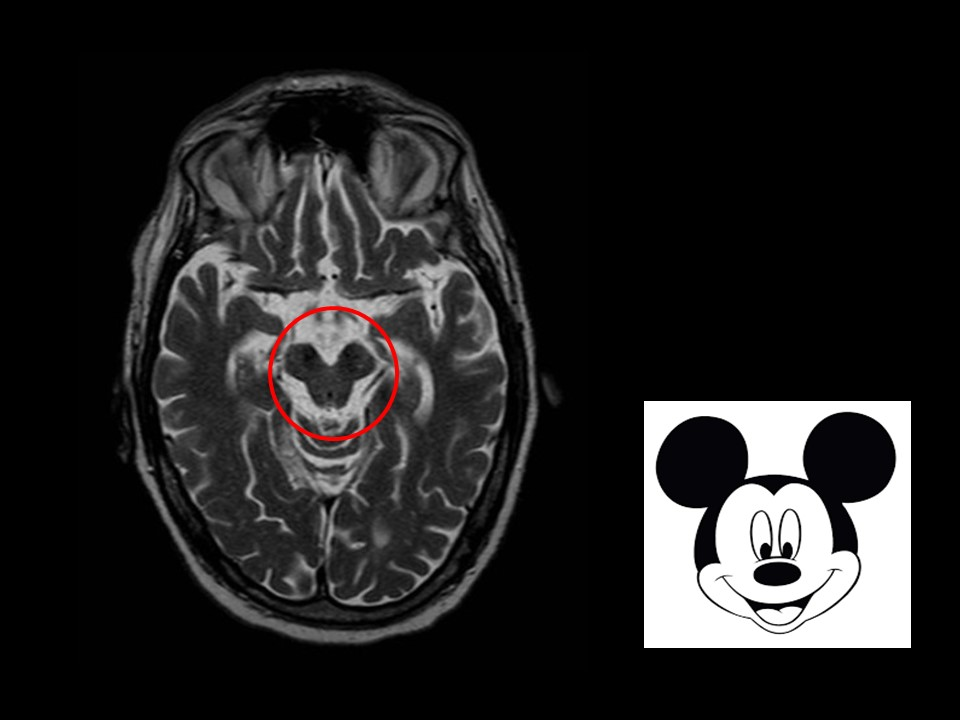

Rostral Midbrain (at Superior Colliculus):

- Most Distinctive Feature: Presence of the large, circular Red Nucleus and the Superior Colliculus. CN III nucleus/fibers are also visible.

- Mnemonic: “Red eyes on Mickey Mouse” (Red Nucleus, CN III ocular motor nucleus, Mickey Mouse shape of cerebral peduncles).